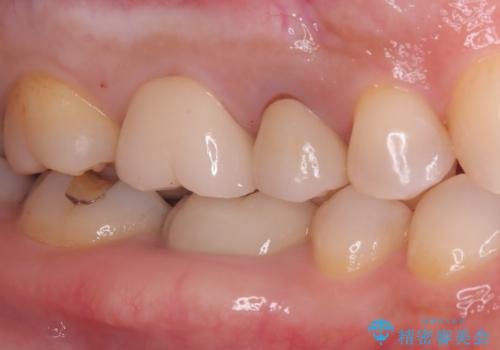

繰り返すプラスチックの欠けを解消。広範囲の修復に適したセラミッククラウン

担当医 河口智英